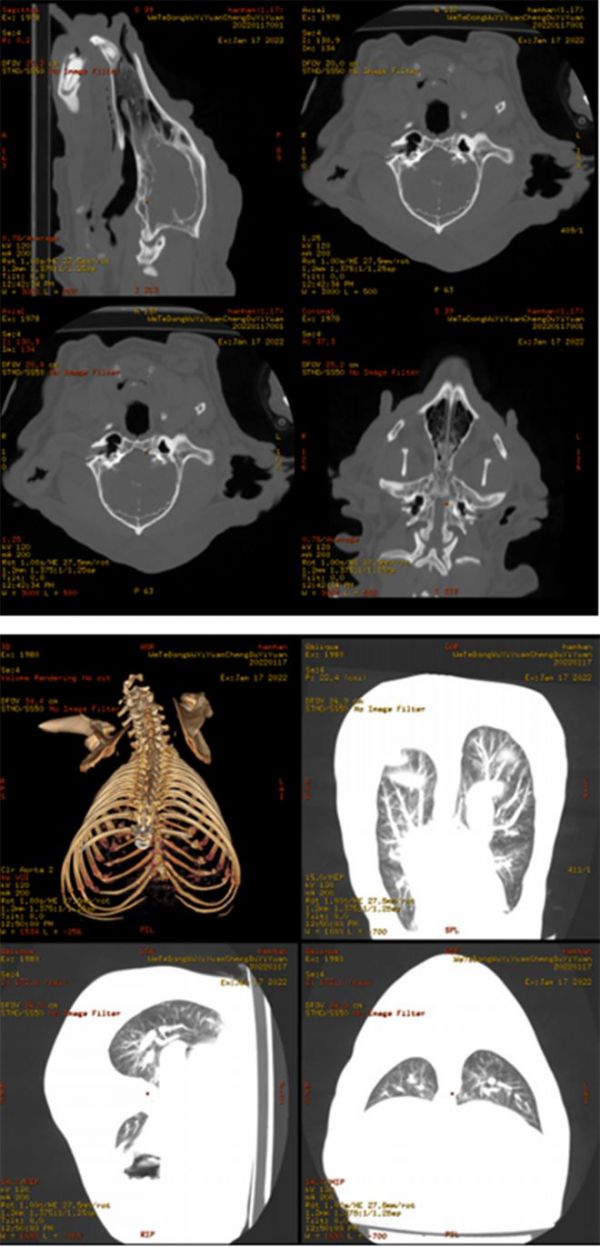

4.4 CT平扫检查

图5. CT检查图片

CT描述

1)双侧鼻甲及鼻道显示对称,鼻中隔居中,双侧鼻窦、额窦及蝶窦内气化良好,粘膜无明显增厚,鼻咽腔对称,颅底骨质未见明显异常。

2)左侧外耳道显示通畅,垂直耳道腔内未见异常密度;水平耳道靠近鼓膜处可见低至等密度异常影像,右侧外耳道扩张,其内充盈等至低密度密度影像,双侧中耳鼓室腔大小对称,密度正常。

3)颈背部皮下可见多个大小不一,软组织密度类圆形影像。

4)胸廓对称,肋骨走行自然,未见畸形及骨质破坏。

5)两肺门未见增大,位置及密度正常。双肺纹理清晰,走行自然,肺叶透过度良好,双肺未见异常密度区。

6)心影形态大小在正常范围,主动脉增粗。

7)影像范围内可见胆囊内高密度影像。

结论

1)外耳炎,右侧严重;

2)颈背部皮下肿块,肺部未见明显转移灶;

3)主动脉增粗,建议结合心脏彩超;

4)胆泥沉积(快形成结石)。

该患宠主人想给患宠做全耳道切除,因为不知道耳道肿物侵袭的范围,不能盲目手术,此时做CT检查尤为重要。CT结果显示,肿物完全堵塞整个耳道,只有耳道入口有严重感染,并未侵袭到内耳,鼓室也较为干净正常。此外还考虑到松狮皮肤松弛的特性,患宠年龄也较大,抵抗力较差,松狮性格特殊,护理困难,建议保守治疗。因为是有菌手术,完全切除整个外耳道,将会暴露中耳和内耳,增加感染内耳的风险。治疗后患宠生活品质得得到明显改善,无异味和渗出,疼痛减轻,主人满意度也较高。